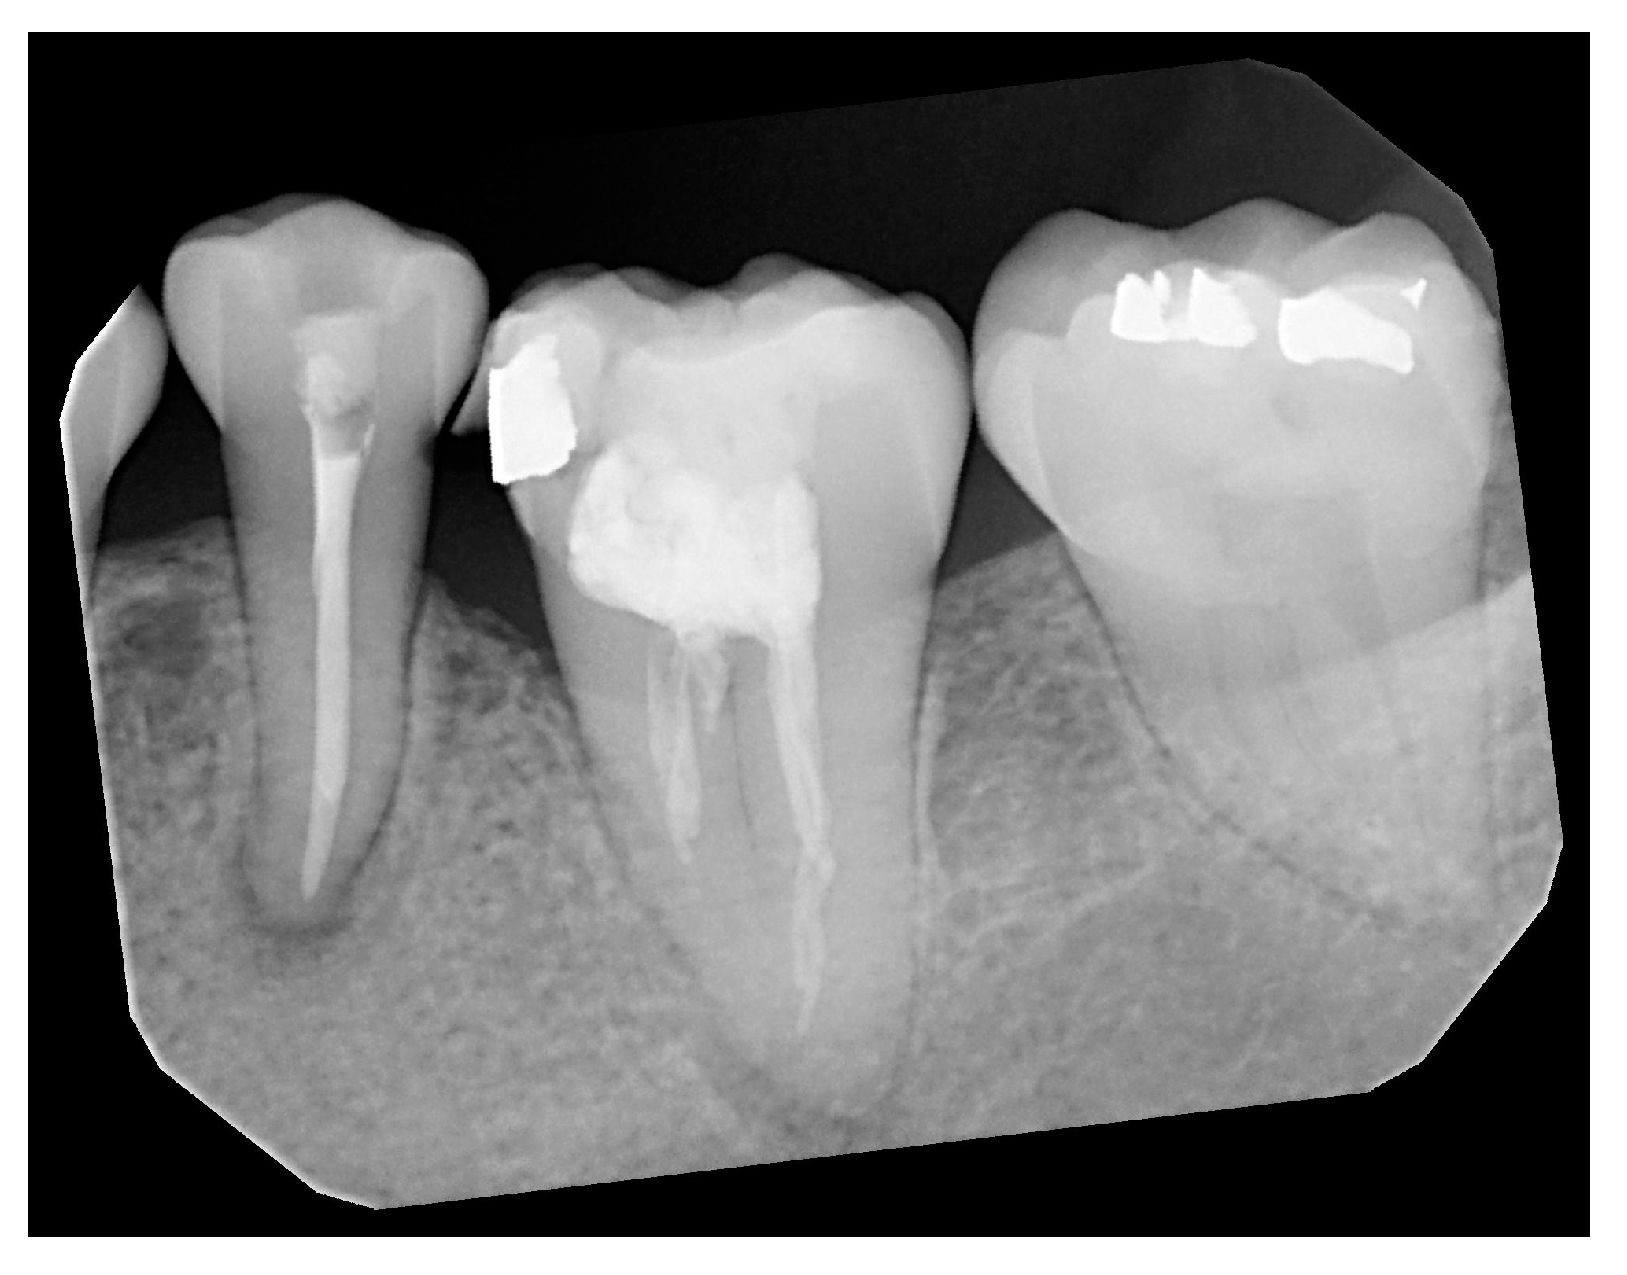

3.1. YOLO Detection and Image Segmentation